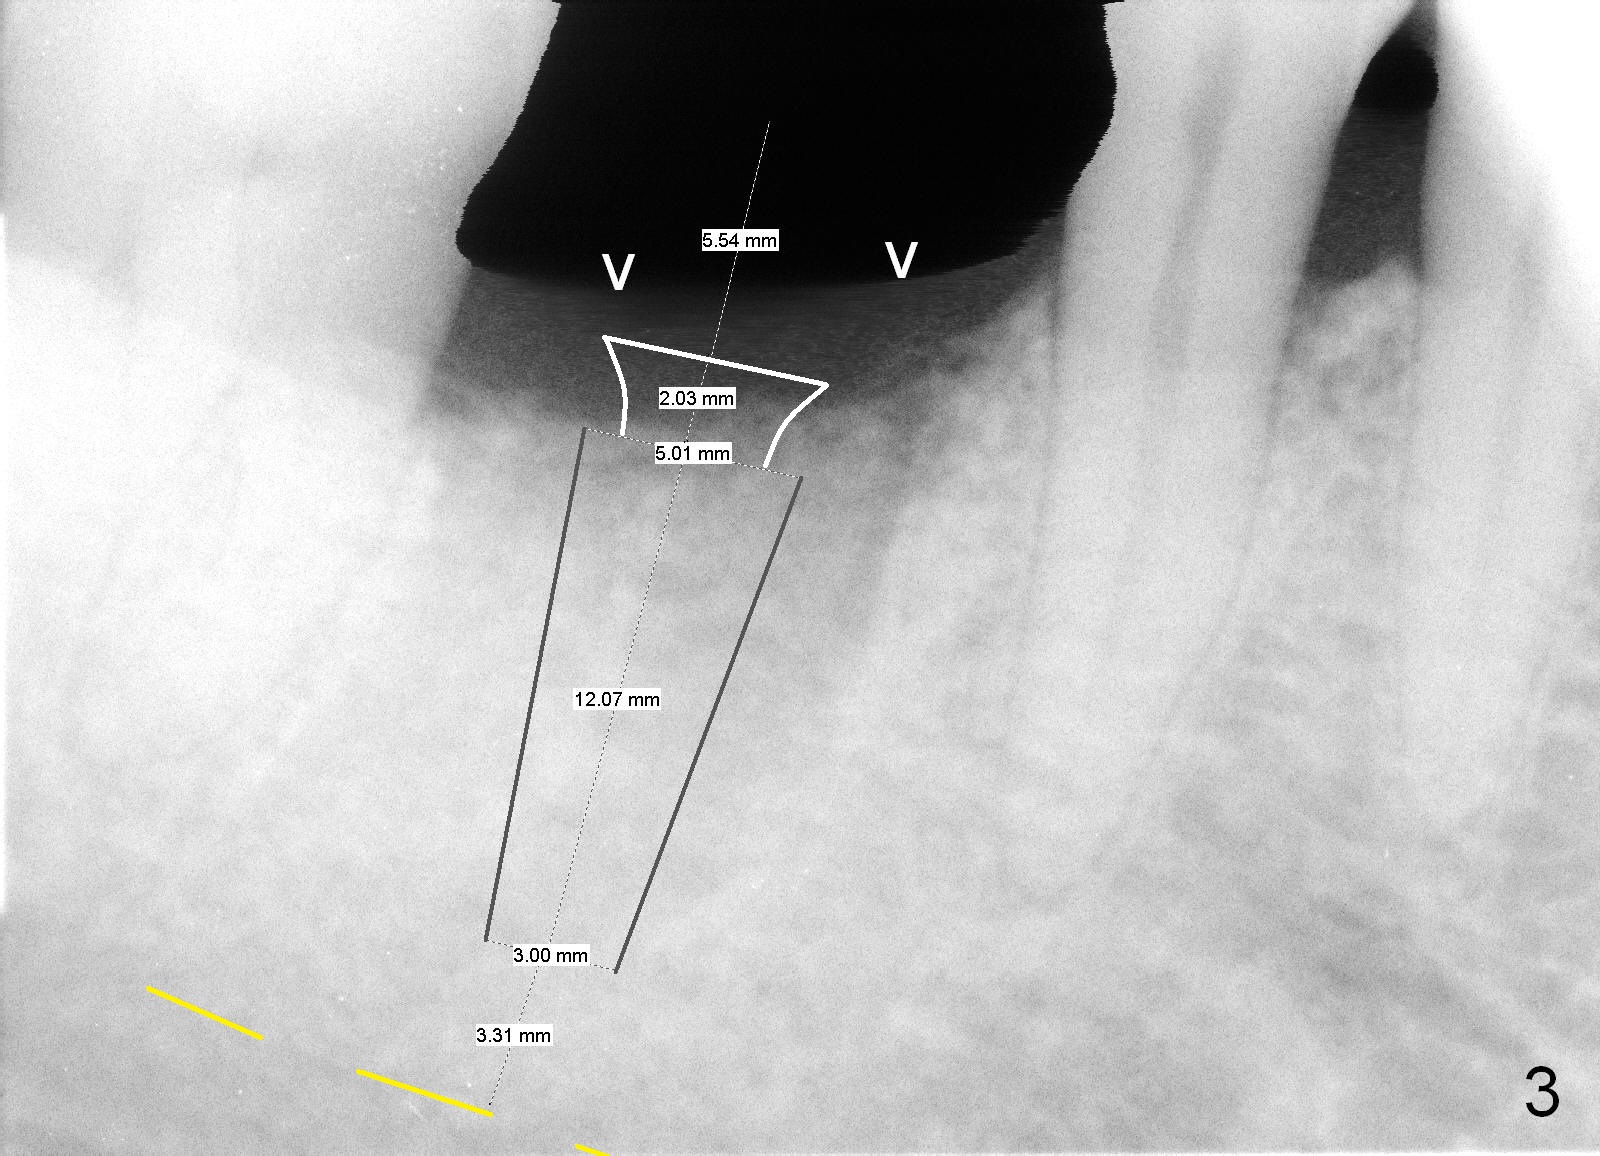

A 44-year-old man lost the tooth #30 three months ago. He is very nervous about the Inferior Alveolar Nerve (Fig.1,3 yellow dashed line). Offer Valium if needed. Check whether there is DO caries of the tooth #29 (Fig.2 <). Finish composite if indicated. There is mild to moderate buccal plate atrophy. The implant may have to be placed slightly lingually. When the insertion torque is high, place an abutment (Fig.3 white inverted cup) with subgingival margin (arrowheads: gingival margin) so that the emergency profile of the crown is better. Make an ideal immediate provisional with good emergency profile and place sutures. The mesial bone may have to be trimmed (Fig.4 red area) so that the abutment is able to be seated without interference. Take photo at each step.